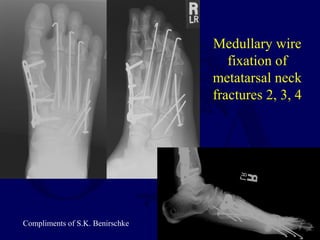

Metatarsal Neck Fractures

This patient sustained

multiple metatarsal neck

fractures after an MVA.

Note additional fractures at

the first and fifth metatarsals

Medullary wire

fixation of

metatarsal neck

fractures 2, 3, 4

Compliments of S.K. Benirschke